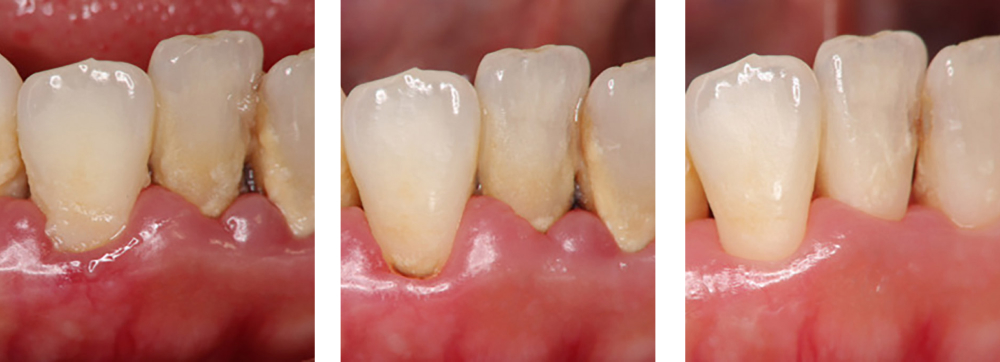

| 治療内容 | 歯磨き指導を行い、歯肉の発赤・腫脹が改善されたため歯石除去を行った |

|---|---|

| 治療期間・回数 | 1カ月・3回 |

| 費用 | 保険適用となります |

| リスク・副作用 |

|